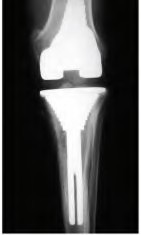

A 60-year-old male tennis player undergoes a unicompartmental knee arthroplasty (UKA) shown in Figures A and B. Which of the following statements regarding this procedure is true?

Figures A and B depict radiographs of a unicompartmental knee arthroplasty (UKA). UKA kinematics have been shown to most closely approximate native knee kinematics.

In an in vitro cadaver study, Patil et al found that TKA significantly changed knee kinematics while the unicompartmental replacement preserved normal knee kinematics.

Fisher et al performed a retrospective study comparing the short-term outcomes of small-incision unicompartmental knee arthroplasty (UKA) with standard total knee arthroplasty (TKA) in 91 consecutive patients older than 70 years. They found: 1) Blood loss was significantly more for the TKA group, as was the need for blood transfusion. 2) Patients with unicompartmental replacements had a much quicker return of function and discontinuation of pain medication. 3) While knee scores and ROM were similar preoperatively, both were better in the unicompartmental group at each postoperative time interval. 4) Narcotic use and length of hospital stay were also significantly less for the unicompartmental group. Therefore answers 2,3,4 and 5 are false.